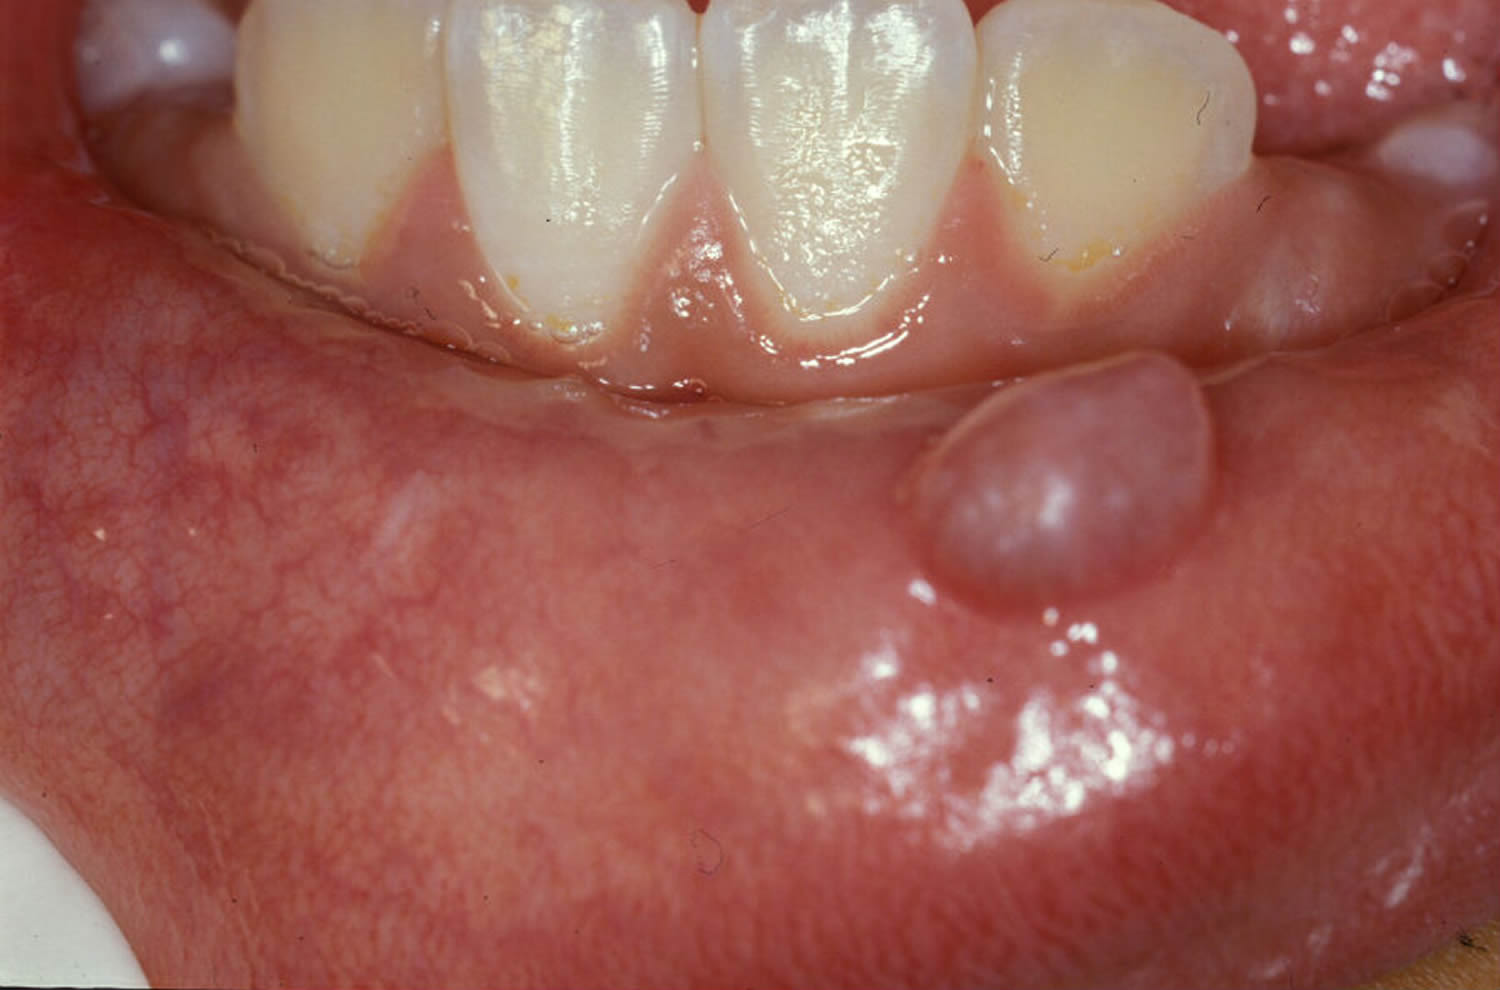

A mucous cyst is a small, raised, bluish-pink swelling that is soft to the touch. They are less than 1 centimeter in diameter and usually occur on the lips, gums, or roof of the mouth. Mucous cysts are not harmful and do not require treatment. However, if they become irritated or infected, they can be painful.

A mucous cyst is a small, fluid-filled sac that forms on the lining of the mouth. They are usually painless and do not cause any problems. However, they can become irritated and bleed easily.